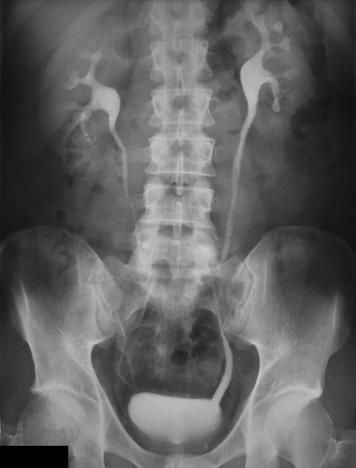

| The right ureter seen in this intravenous pyelogram shows hydroureter in a patient with vesicoureteral reflux (VUR). Incompetence of the vesicouretreal valve may be due to a congenital malposition or shortening of the intravesicle portion of the ureter. Loss of bladder muscle tone from neuropathy may also lead to VUR. The reflux leads to hydroureter and hydronephrosis; the risk for infection is increased. |